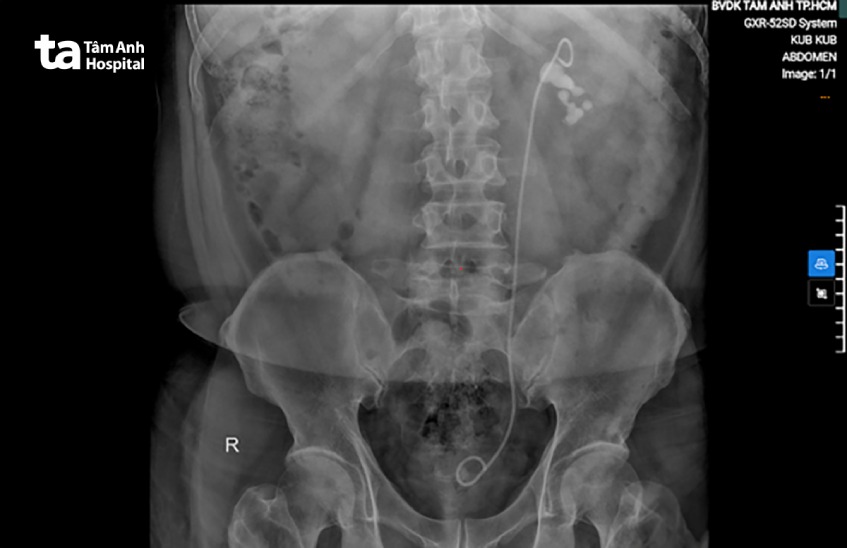

Bằng cách chụp x-quang, bác sĩ có thể quan sát rõ hình ảnh của sỏi. Từ đó biết được vị trí, số lượng, mật độ, kích thước của những viên sỏi. Điều này hỗ trợ bác sĩ cân nhắc lựa chọn phương pháp điều trị phù hợp dựa trên tình trạng sức khỏe của người bệnh và hình ảnh sỏi thận trên x-quang.

Chụp x-quang không thuốc cản quang thường được bác sĩ chỉ định để phát hiện sỏi cản quang đường tiết niệu ở những vị trí như niệu đạo, bàng quang, niệu quản, bể thận, đài thận. Bên cạnh đó, phương pháp này còn giúp bác sĩ xác định bóng thận hoặc chẩn đoán phân biệt bệnh đau vùng xương cụt, lưng, thắt lưng với tình trạng đau do sỏi tiết niệu, sỏi thận.

Các loại sỏi thận và đặc điểm hình ảnh trên x-quang hệ niệu không thuốc cản quang: